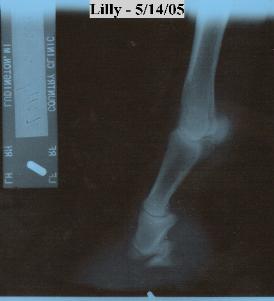

Lily's distal phalanx (coffin

bone) fell out of her right

hind foot.  Lily is

completely sound at the

trot, and canter without

any problems.